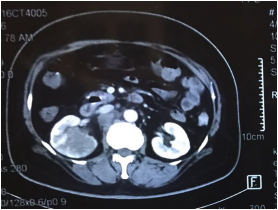

患者为64岁女性。主诉右侧腰痛4个月,疼痛呈间歇性,自发复发,无明显诱因。患者否认有血尿、肿块和消瘦。没有类癌综合征的症状。除了高血压,患者无其他病史。全身检查显示右肾区有轻微叩诊痛,腹部无明显肿块。生化指标及血常规正常。计算机断层扫描(CT)显示一个低密度肿块(最大直径50mm),在右肾下极有缓慢的增强和模糊的边界。同时还显示多发性腹膜后淋巴结肿大(图1)。正电子发射断层扫描(PET)观察到在右肾下极观察到氟脱氧葡萄糖(FDG)的异常摄取。因此,被诊断为恶性肾肿块、多发性主动脉旁淋巴结转移。

图1. 右肾的CT表现。CT扫描显示一低密度肿块,直径50mm,右肾下极有增强,腹膜后有淋巴结肿大